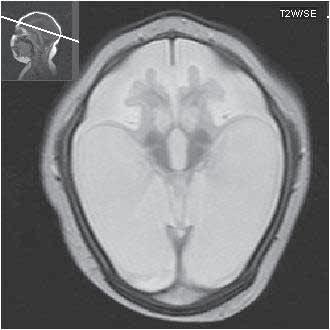

Obr. I.1.4a Lissencefalie typ I

Obr. I.1.4b Frontálně naznačená gyrifikace (šipka), kůra je nápadně tenká, vrstva bílé hmoty (přerušovaná šipka) odděluje mozkovou kůru od silné, vnitřní vrstvy šedé hmoty mozkové, lissencefalie typ I; stejný pacient jako na obr I 1 4a c d

Obr. I.1.4c Lissencefalie typ I

Obr. I.1.4d Lissencefalie typ I; stejný pacient jako na obr I 1 4c

Obr. I.1.4e Tenká mozková kůra (šipka), vrstva bílé hmoty (přerušovaná šipka), která odděluje kůru od silné subkortikální šedé hmoty (černá šipka), lissencefalie typ I

Obr. I.1.4f Tenká mozková kůra (šipka), vrstva bílé hmoty (přerušovaná šipka), která odděluje kůru od silné subkortikální šedé hmoty (černá šipka), lissencefalie typ I; stejný pacient jako na obr I 1 4e